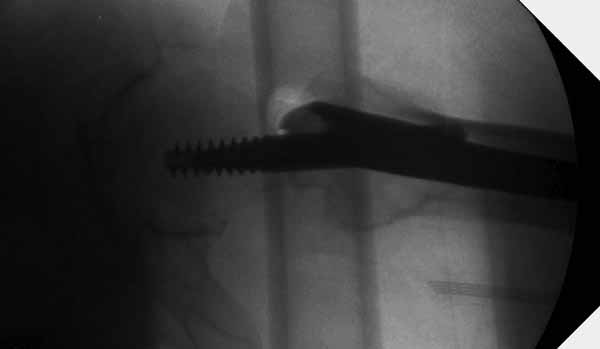

Первые снимки показывают технические погрешности установки DHS. Не была достигнута репозиция, конечность в флексии и шейка в ротации. Сегодня все меньше обращают внимание на параметры для оценки репозиции (S контуры Lowell в обеих проекциях и Garden Alignment Index, в норме 155 и 180 градусов), хотя такие простые тесты помогли бы дорепонировать смещение. Винт находится сзади в головке, что при нагрузке поменяет вектор и вместо компрессии в линии перелома срежет головку-Cut Out!

В зависимости от дистанции линии перелома и латерального кортекса надо использовать разной длины barrel, т.е. конец баррели не должен доходить до пределов перелома. Здесь конец длинного ствола упирается в медиальный фрагмент, что мешает созданию компрессии, а более короткий barrel создал бы запас для компрессии. В боковой пластине вместо 4х можно было ограничится двумя шурупами, потому что головка шурупа в 4.5 мм выдерживает давление до 350 кг.